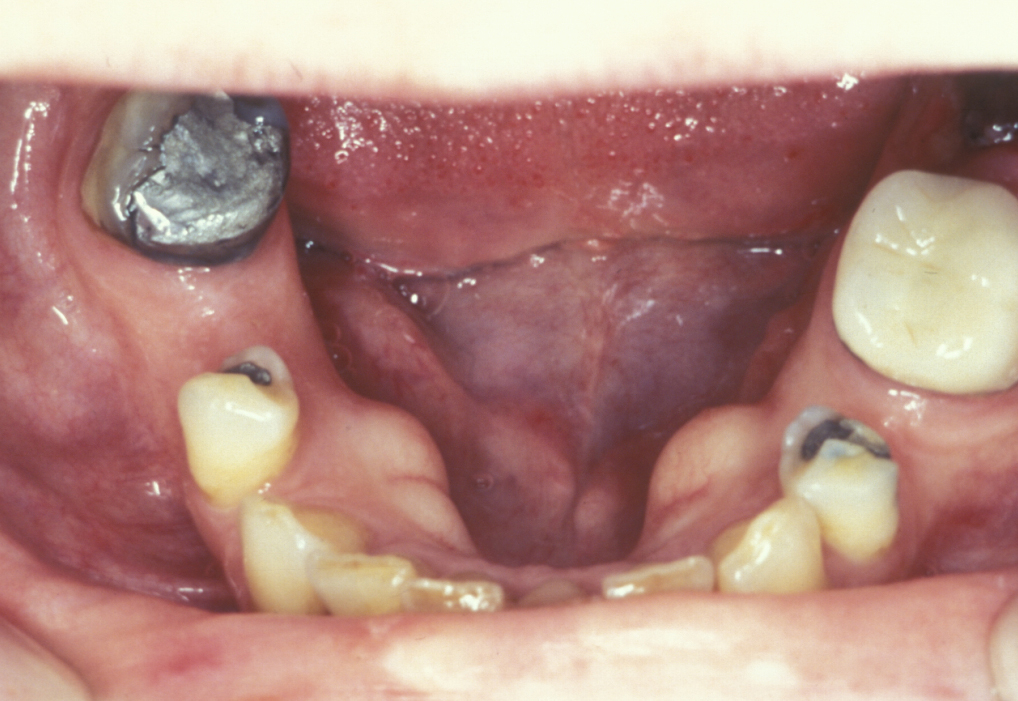

Torus

A torus is a bony exostosis (outgrowth) of the jaw. Torus palatinus occurs in the centre of the hard palate (see Figure 9), torus mandibularis occurs in the lingual (tongue-side) premolar or molar region of the mandible (see Figure 10). These lesions are entirely benign and only require removal when they are symptomatic or for reasons of prosthetic functionality.

Figure 9: The appearance of torus palatinus.